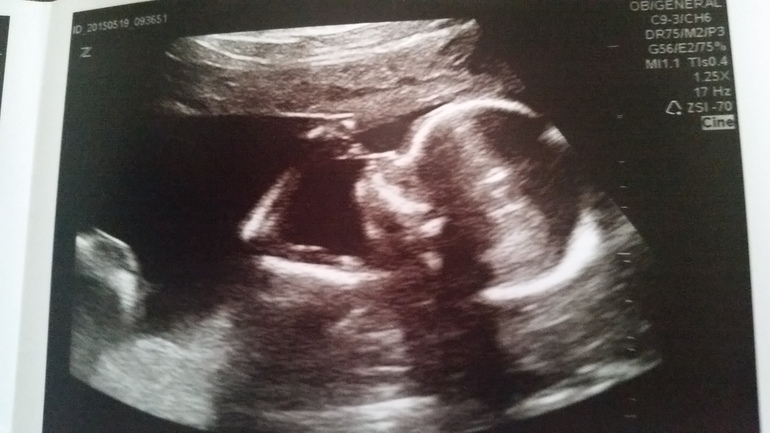

Узистка осталась довольна увиденным, подтвердила, что точно девочка и с трудом замерила все необходимое. Весим мы 190 грамм, имеем все пальчики и остальные красивые части тела. Фотки сильно так себе из-за неуловимости пациента.